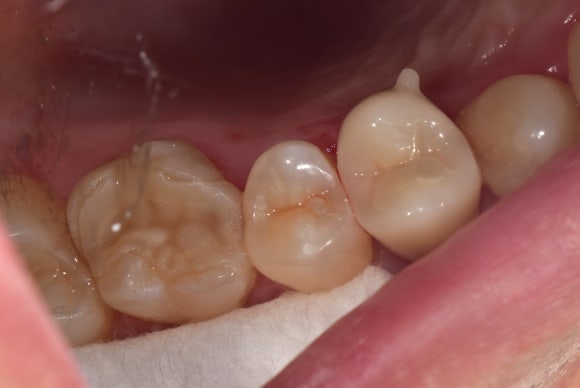

20250421

크라운이 얹혀질 머리가 완성되었습니다.

어디까지가 치아이고 어디까지가 레진인지

구분이 안될 정도로 꼼꼼하게 쌓여올렸습니다.